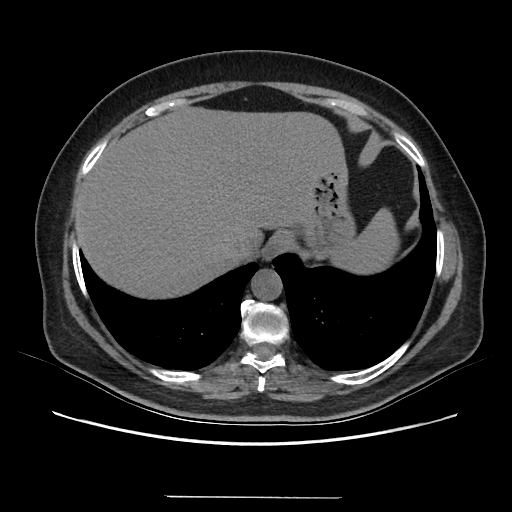

Generated VENOUS CT scan (A→B translation)

Full window (WL 1023.5, WW 4095 β†’ Low βˆ’1024, High +3071)